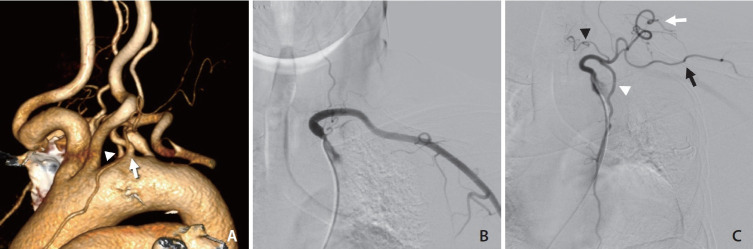

We report a rare case of a left internal mammary artery (LIMA) originating from the left thyrocervical trunk (TCT), which arose directly from the aortic arch. A patient in their 70s presented with bilateral distal internal carotid artery aneurysms, diagnosed through computed tomography angiography performed for headache evaluation. Transfemoral cerebral angiography confirmed the aneurysms and incidentally revealed the anomalous origins of the TCT and LIMA, as well as a left vertebral artery directly arising from the aortic arch. This case emphasizes the importance of recognizing such rare anatomical variations prior to diagnostic or interventional procedures. Thorough preoperative evaluation is critical to avoid complications, particularly in coronary artery bypass grafting and head and neck tumor embolization.